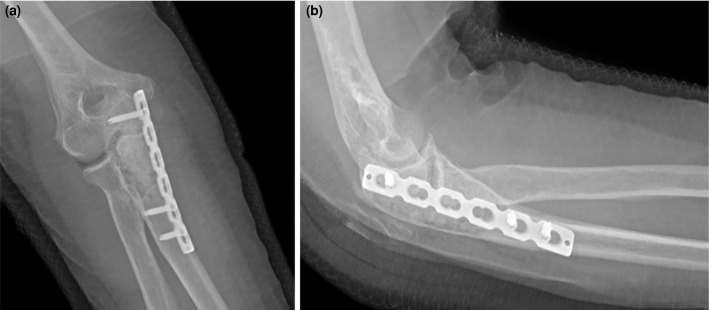

骨内神经鞘瘤是一种极为罕见的良性肿瘤,起源于周围神经系统的雪旺细胞。虽然这些肿瘤常见于下颌骨和骶骨,但它们发生在长骨,特别是尺骨,是罕见的。59岁女性患者因右肘疼痛和肿胀两年入院。x线影像学显示尺骨近端干骺端皮质扩张和变薄的溶解性病变,而磁共振成像显示不规则边界病变通过皮质侵蚀延伸到关节。鉴别诊断包括单纯性骨囊肿、内生纤维瘤、巨细胞瘤和转移。手术包括刮除和植骨,病理诊断为骨内神经鞘瘤。免疫组化染色显示SOX10和S100阳性表达,证实诊断。术后恢复顺利,患者在6个月的随访中恢复了全活动能力,无疼痛。总之,这个病例强调了在良性骨病变鉴别诊断中考虑骨内神经鞘瘤的重要性,特别是在罕见的部位,如尺骨。组织病理学检查仍然是准确诊断的必要条件。

Intraosseous schwannomas are extremely rare benign tumors originating from Schwann cells of the peripheral nervous system. While these tumors are commonly found in the mandible and sacrum, their occurrence in long bones, particularly the ulna, is uncommon. A 59-year-old female patient was admitted with a two-year history of pain and swelling in her right elbow. Radiographic imaging revealed a lytic lesion with cortical expansion and thinning in the proximal ulna metaphysis, while magnetic resonance imaging showed a lesion with irregular borders extending into the joint via cortical erosion. Differential diagnoses included a simple bone cyst, enchondroma, giant cell tumor, and metastasis. Surgical procedure involved curettage and bone grafting, and the lesion was diagnosed histologically as an intraosseous schwannoma. Immunohistochemical staining showed positive expression of SOX10 and S100, confirming the diagnosis. Postoperative recovery was uneventful, and the patient regained a full range of motion without pain at her six-month follow-up. In conclusion, this case underscores the importance of considering intraosseous schwannoma in the differential diagnosis of benign bone lesions, particularly in rare locations such as the ulna. Histopathological examination remains essential for an accurate diagnosis.